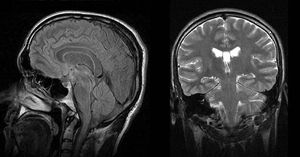

Narcolepsy is a long-term neurological disorder that involves a decreased ability to regulate sleep-wake cycles. Symptoms include periods of excessive daytime sleepiness that usually last from seconds to minutes and may occur at any time. About 70% of people also experience episodes of sudden loss of muscle strength, known as cataplexy. These spells can be brought on by strong emotions. Less commonly there may be inability to move or vivid hallucinations while falling asleep or waking up. People with narcolepsy sleep about the same number of hours per day as people without, but the quality of sleep tends to be worse. Image: Normal cranial MRI images (sagittal FLAIR and coronal T2W images, respectively) in patient with narcolepsy. @medicalcortex #medstudent #nurse #doctor #surgery #surgeon #medicine #premed #usmle #med #stress #exams #neurology #neuroscience #study #motivation #motivated #amman #jordan #book #dopamine #medicalbooks #serotonin #psychology #psychiatrist